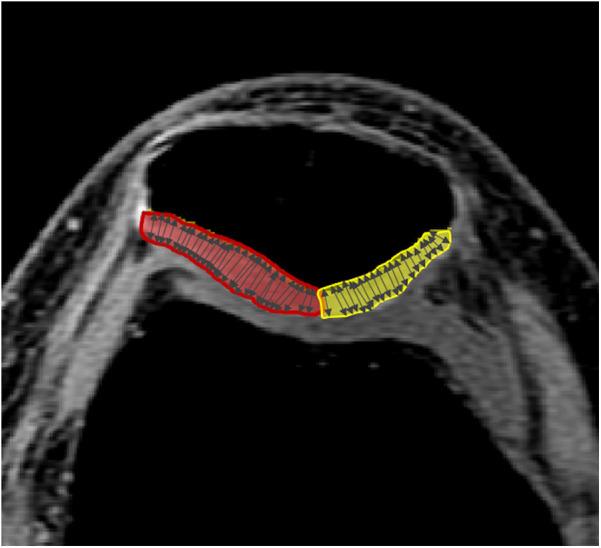

The relationship between patellofemoral cartilage morphology and knee external rotation (KER), one of the possible factors increasing patellar cartilage stress, has been rarely explored in individuals with and without patellofemoral pain (PFP). Ten individuals with PFP and 10 pain-free controls, matched for age, weight, height, and activity level, participated. Patellar cartilage morphology was assessed using 3-Tesla magnetic resonance imaging. Lower extremity kinematics during bilateral squatting at 45° of knee flexion were captured using a 3-dimensional motion capture system. Pearson and Spearman correlation coefficients were used to assess the associations between cartilage thickness (medial, lateral, and total) and peak KER, along with other peak joint angles across the three planes. Across all participants, there were significantly moderate correlations between medial cartilage thickness and KER ( = -0.48,  = 0.03), and total cartilage thickness and KER ( = -0.47,  = 0.35). In the PFP group, there was a significantly large correlation between medial cartilage thickness and KER ( = -0.66,  = 0.03). In the control group, there was a significant very large correlation between lateral cartilage thickness and KER ( = -0.79,  = 0.01) and a significant very large correlation between total cartilage thickness and KER ( = -0.75,  = 0.01). The findings suggest that thinner patellar cartilage is associated with increased KER during bilateral squatting in persons with and without PFP. Since our study focused on a double-limb activity, which may require less KER, future research should examine its impact on cartilage morphology during single-limb activities.

髌股关节软骨形态与膝关节外旋(KER)之间的关系,是增加髌软骨应力的可能因素之一,在有和没有髌股关节疼痛(PFP)的个体中很少被研究。10名患有PFP的个体和10名年龄、体重、身高和活动水平相匹配的无疼痛对照者参与了研究。使用3特斯拉磁共振成像评估髌软骨形态。在膝关节屈曲45°的双侧深蹲过程中,使用三维运动捕捉系统记录下肢运动学数据。使用Pearson和Spearman相关系数评估软骨厚度(内侧、外侧和总厚度)与峰值KER之间的关联,以及三个平面上的其他峰值关节角度之间的关联。在所有参与者中,内侧软骨厚度与KER之间存在显著的中度相关性(r = -0.48,p = 0.03),总软骨厚度与KER之间也存在显著的中度相关性(r = -0.47,p = 0.35)。在PFP组中,内侧软骨厚度与KER之间存在显著的强相关性(r = -0.66,p = 0.03)。在对照组中,外侧软骨厚度与KER之间存在显著的极强相关性(r = -0.79,p = 0.01),总软骨厚度与KER之间也存在显著的极强相关性(r = -0.75,p = 0.01)。研究结果表明,无论有无PFP,在双侧深蹲过程中,较薄的髌软骨与增加的KER相关。由于我们的研究集中在双下肢活动,这可能需要较少的KER,未来的研究应检查其对单下肢活动期间软骨形态的影响。